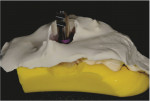

After ensuring that the wax was smooth to the top of the implant analog head, a temporary abutment (RC Temporary Abutment, Straumann) was air abraded and screwed into the analog. A bis-acryl composite resin (3M™ Protemp™, 3M Oral Care) was then injected around the abutment to the level of the gingival margin (Figure 15). Once polymerized, the abutment was removed from the cast, and it was observed that the resin flowed completely to the base (Figure 16). The transition between the base of the abutment and the gingival margin was then smoothed (Figure 17). To complete the custom healing abutment, the subgingival portion of the restoration was polished, and the protruding abutment was cut off and made smooth with the top surface (Figure 18). When compared with a stock healing cap, a custom healing abutment fabricated with this technique will look wide and flat.

The completed custom healing abutment was disinfected and delivered into the patient's mouth (Figure 19). The screw was hand torqued, and the access was sealed with sterile polytetrafluoroethylene tape and composite resin (Venus® Diamond, Kulzer). If sutures are present, it is important to ensure that they are not under too much tension. The patient was dismissed with instructions to avoid placing any occlusal forces on the restoration and to carefully but thoroughly clean the area during hygiene.